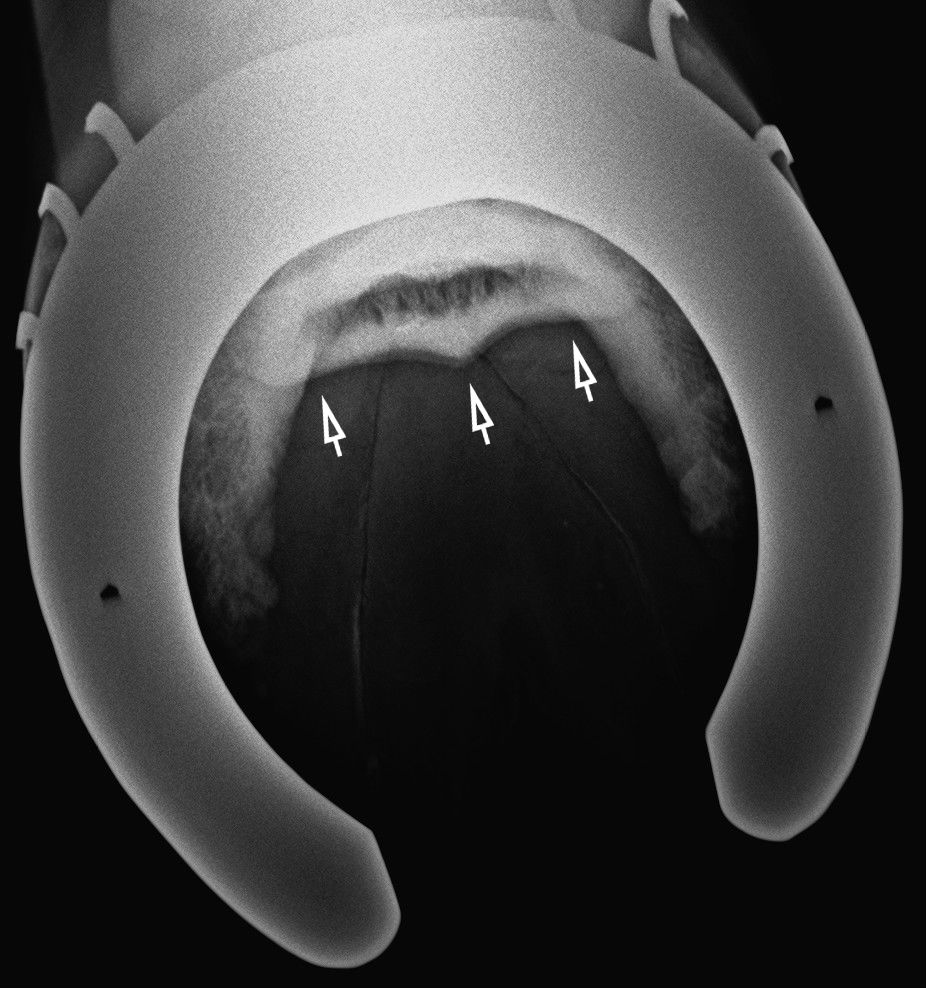

A másik nyírcsont felvétel, a skyline. Úgy készül, hogy a lovat ráléptetjük a kazettára. A nyilak mutatják a csont helyeződését.

Normális nyírcsont. Jól elkülönülő vékony, fehér kéregállomány és sötétszürke velőállomány, benne vékony csatornácskák.

Kitágult csatornák (vékony nyilak) és oldódás a csont kéregállomáányában 8 vastag nyíl).

Nagymértékben kitágul, cisztává váló csatornácskák.

A kéreg- és velőállomány egybeolvad a súlyos fokú meszesedés miatt. Középen cysta.